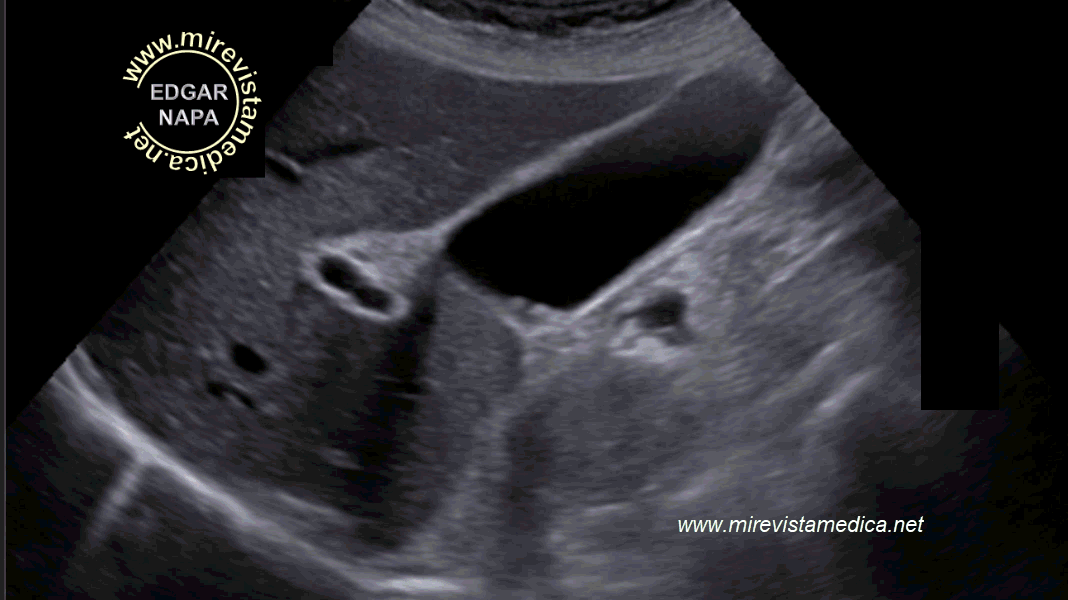

Hallazgos por ultrasonido (US_) :

- imagen hiperecogénica, movil, de márgenes circunscritos que deja sombra acústica posterior (litiasis).

- Signo de Murphy ecográfico. Pain and tenderness with transducer pressure directly over gallbladder.

- Engrosamiento de pared vesicular (se le denomina así cuando es > 3 mm). Hazy delineation of GB wall with echogenic pericholecystic fat.